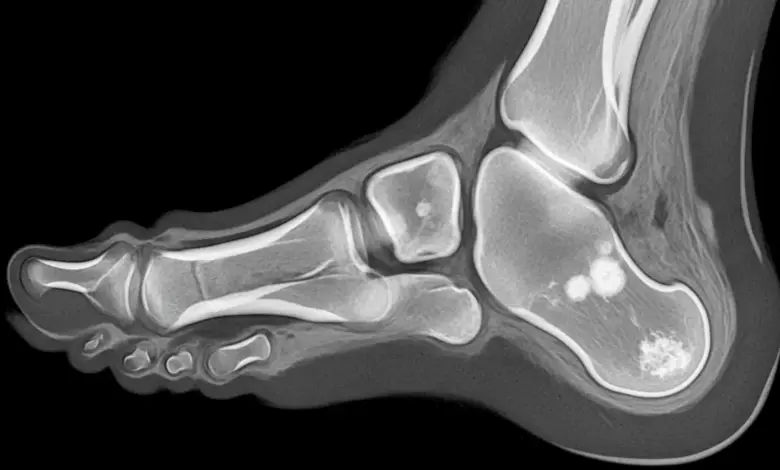

O raio X pode mostrar achatamento e esclerose da cabeça metatarsal, enquanto a ressonância magnética detecta edema ósseo, áreas de necrose e ajuda a estadiar a doença de Freiberg nas fases iniciais.

Em linhas gerais, os estágios iniciais apresentam apenas edema e pequenas fissuras, à medida que os estágios avançados cursam com colapso da superfície articular e deformidade.